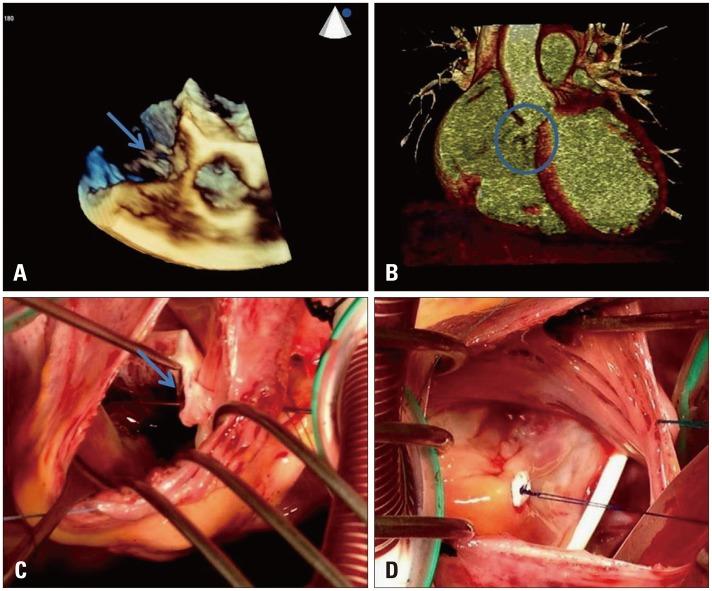

J Cardiovasc Ultrasound. 2016 Mar;24(1):84-6. doi: 10.4250/jcu.2016.24.1.84. Epub 2016 Mar 24.